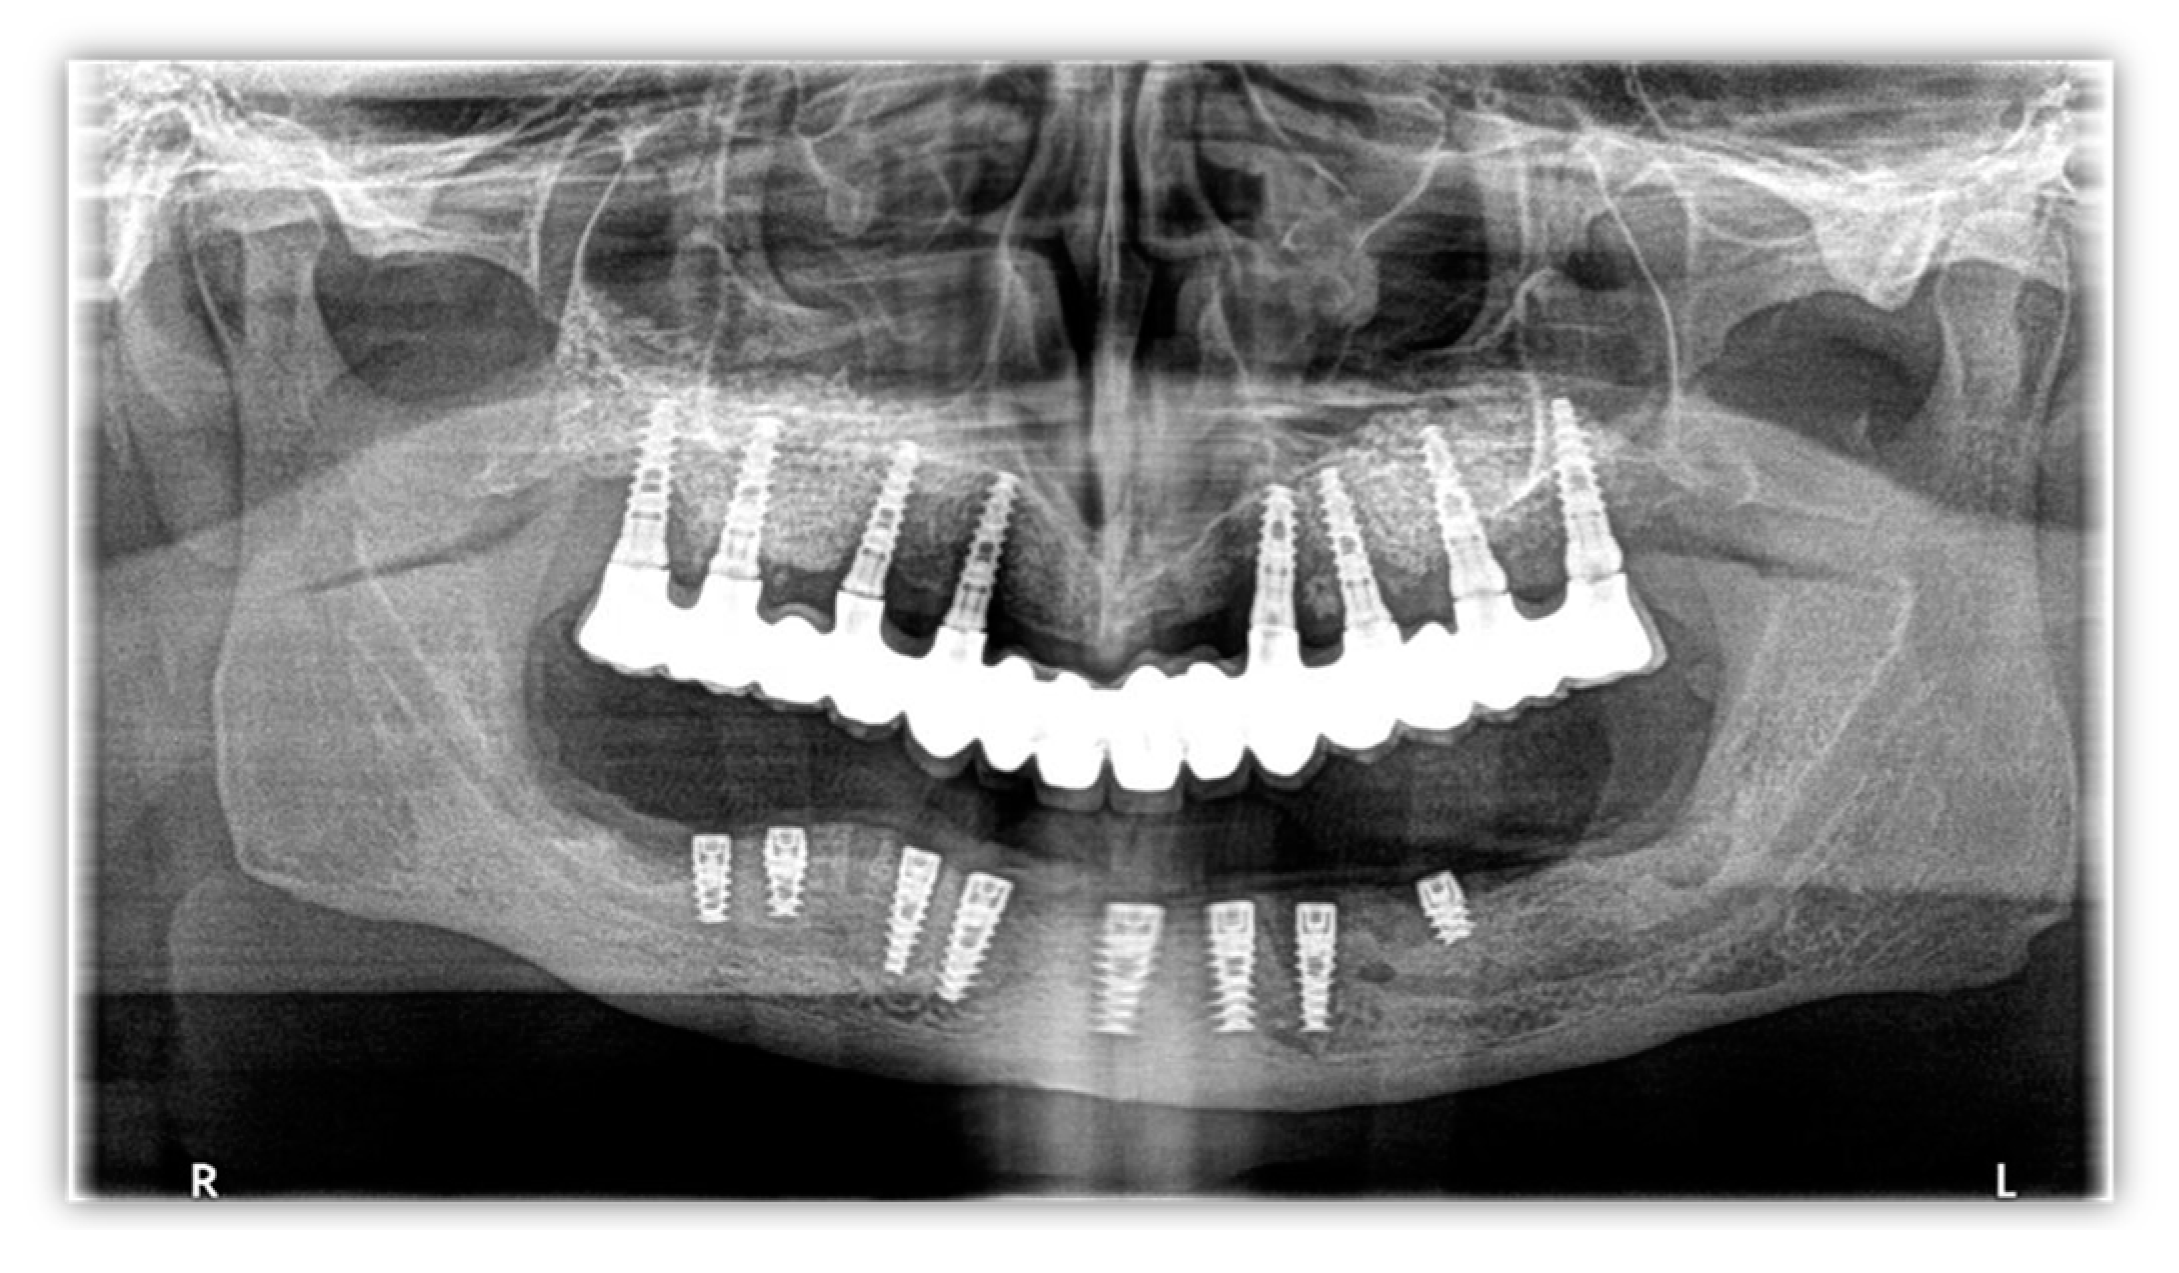

A 58-year-old man with a history of implant surgery (Figure 1) and implant failure on the mandible, leading to significant bone loss, was referred to us for bone restoration and functional loading.

Figure 1.

Orthopantomography image from 2014.